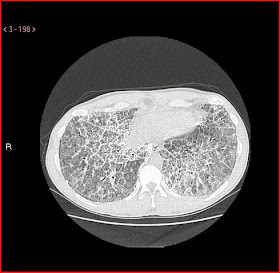

caso 2 (AMN)

Varón de 40 años , interno en prisión, remitido con diagnóstico de neumonía bilateral con hipoxemia marcada y pérdida de 10kg en 1 mes.